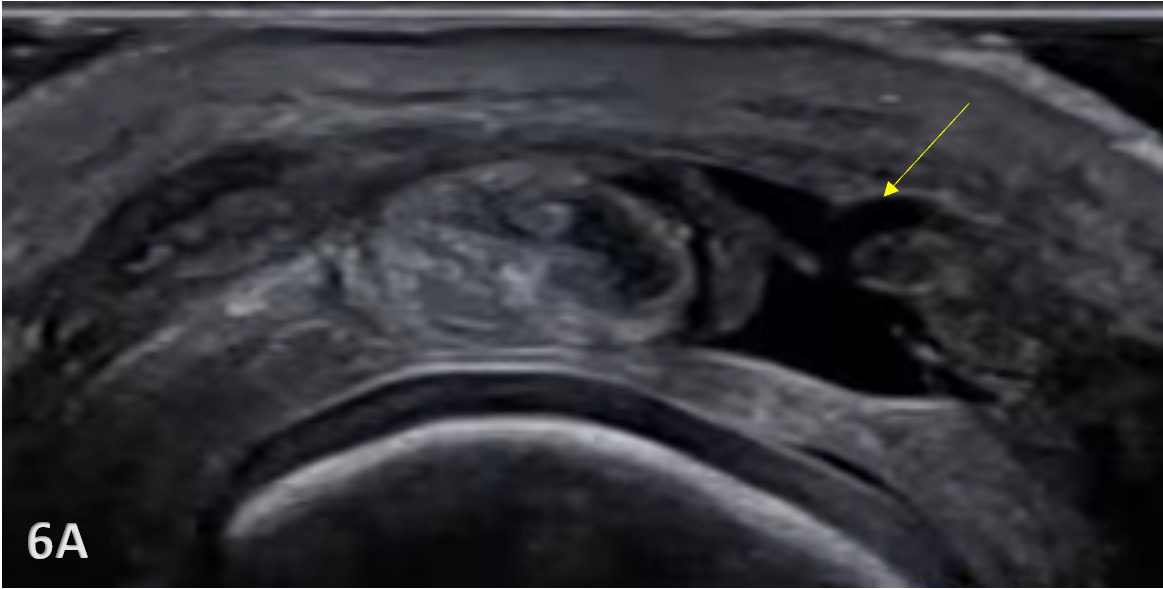

Because the superficial skin on the dorsal surface of the hand is thin, and the tendons are located superficially, they are susceptible to laceration and or avulsions from trauma. A sagittal band rupture known as “Boxer’s knuckle” can also be seen due to direct trauma or repetitive microtrauma to the MCP joint.1 With Boxer’s knuckle, the most affected finger is the 3rd, with the tendon seen dislocating ulnarly. With lacerations, obviously, an incision will be seen. However, with Boxer’s knuckle and an avulsion fracture, the injury may be closed. Pain, swelling, and diminished function of the suspected tendon will be present as the major signs and symptoms.

Pathologic Findings in Extensor Tendon Injury

Hypoechoic thickening due to swelling and edema.

Disruption of fibrillar pattern in partial tears and ruptures.

Cortical irregularity and interruption in bony avulsions of insertion.

Associated edema and effusion.